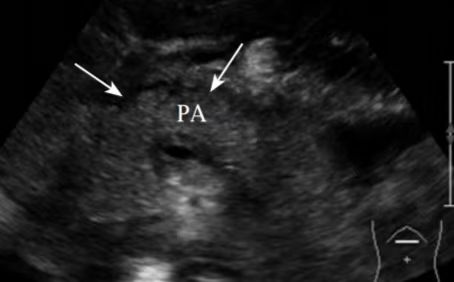

对于轻症胰腺炎,其超声表现主要为: 胰腺弥漫性或局限性肿大、内部回声增强、分布不均匀。

对于重症胰腺炎,其超声表现主要为:

●胰腺肿大更加明显、边缘不规则,边界不清楚,呈断续状。

●胰腺内部呈强回声、弱回声及无回声混杂的不均质改变。

●由于周围渗出及其周围组织水肿,胰腺周边可见一层弱回声带。

●胰周积液或胰腺假性囊肿形成。

●部分还可伴有胸腹腔积液。